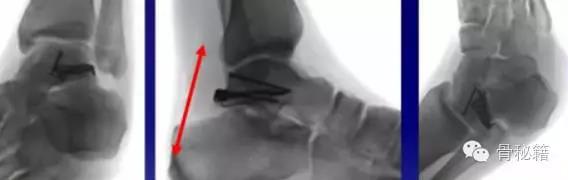

除去关节面的地方,就是我们最适合置放内固定的地方主要位于内侧和外侧

手术入路1、内侧入路比较安全,注意大隐静脉和隐神经

骨折十分粉碎时可采用内踝截骨事先可进行螺钉的拧入,类似鹰嘴截骨

2、外侧入路

对于颈部的骨折,如果一侧钢板的位置不佳,则容易造成另外一侧的骨折裂开所以最好的固定是一侧用钢板固定,另外一侧可采用螺钉进行加压,避免另外一侧开口

3、后侧入路:对于特殊的后侧距骨骨折

两侧切口无法进行复位可采用后侧入路进行复位以及固定